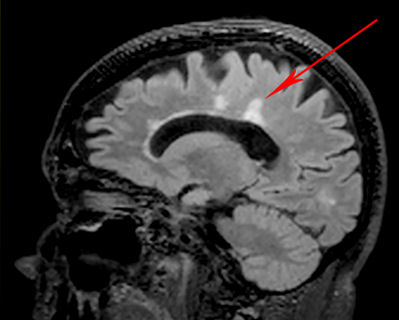

Caps and Bands Typical Dawson finger aspect Virchow Robin spaces Artefact Diffuse non-MS lesion